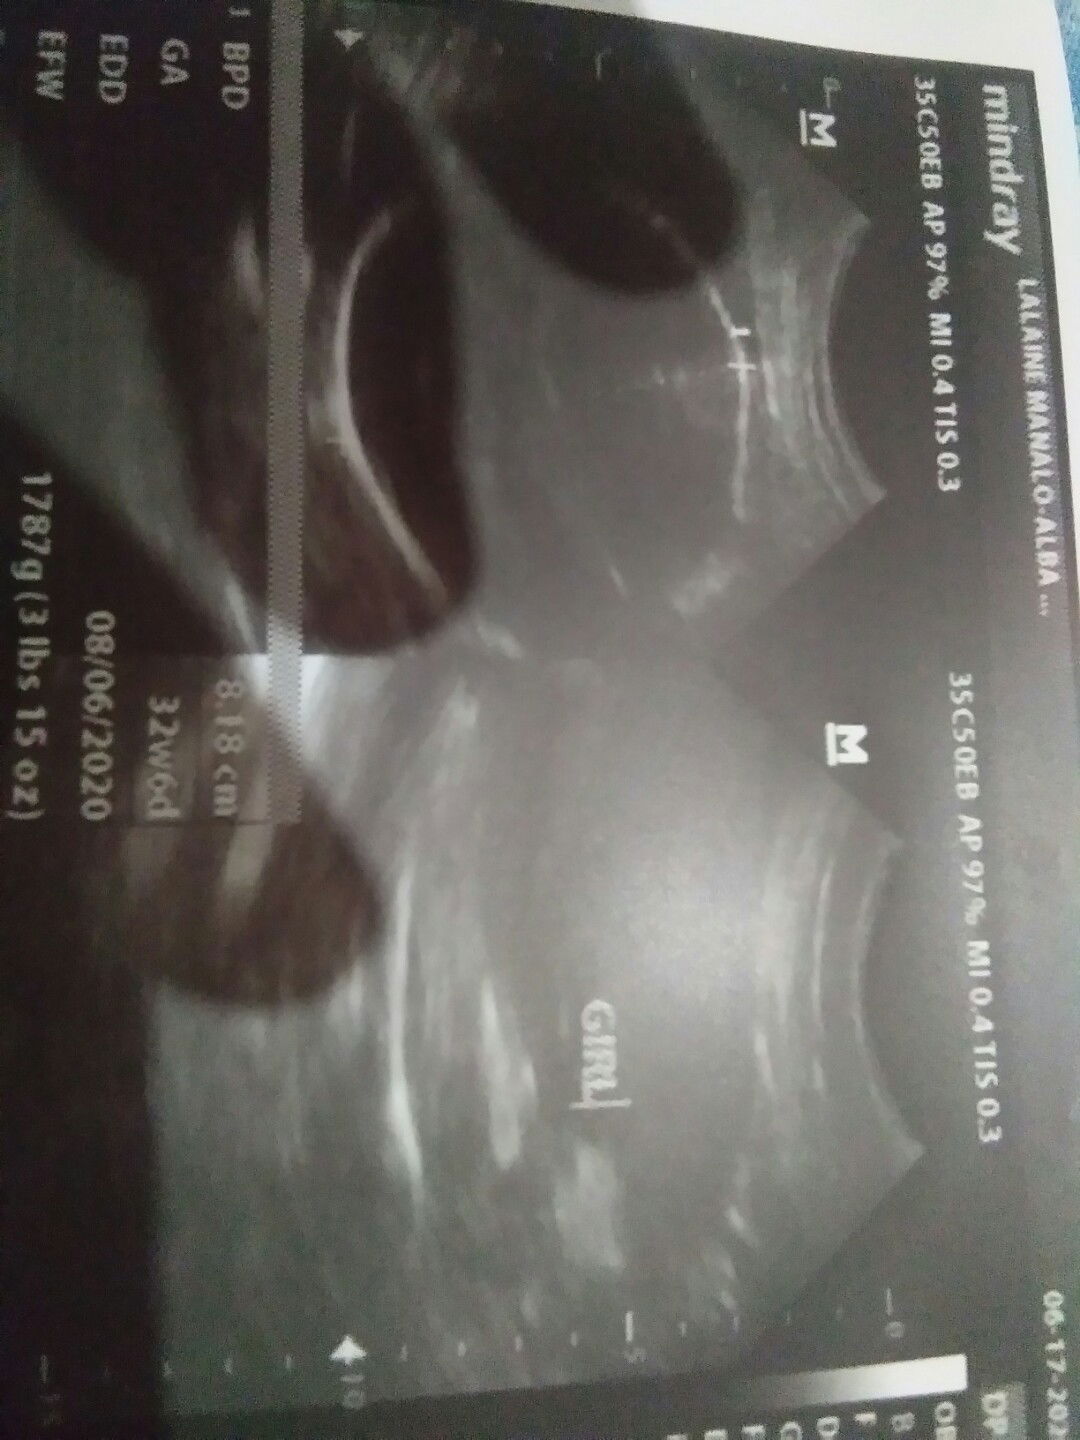

Baby girl mia

Edd: september 25, 2020 Dob: september 21, 2020 Timecheck: 11:29 p.m. Welcome to the outside world my baby MIA NATHALIA BIANCA VERGARA PEREZ 👶 Thankyou lord for giving me lovely daughter and also dinyo po kami pinabayaan. Worth it lahat ng sakit ng paglalabor buti dimoko pinahirapan mahal at 20minutes labor ng sobra then yun lumabas kana agad 💖 thanku po😇 Sa mga kabuwanan napo have a safe delivery mga ka mommies😊 kaya nyorin po yan! - RM RN MATERNITY CLINIC ❤ #firstbaby #1stimemom